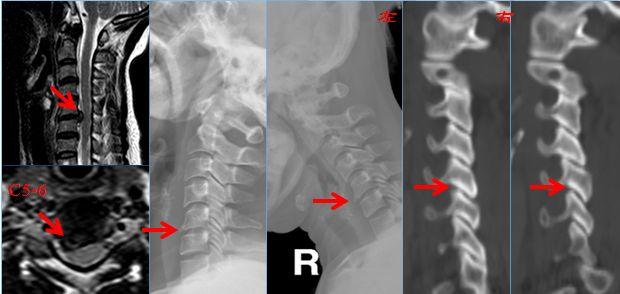

典型案例

黄某,女,39岁,颈痛伴左上肢放射痛及麻木感1年,诊断为神经根型颈椎病。行颈5-6椎间盘切除减压、人工椎间盘置换术。

术前X线、CT、MRI提示颈5-6椎间盘右后型突出并神经根受压。

颈5-6人工椎间盘置换术后,颈椎手术节段运动可以继续保留。